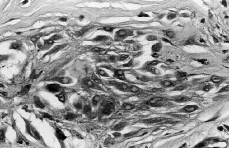

Las células névicas mostraban citoplasma eosinófilo abundante con morfología fusiforme o epitelioide, con escaso pigmento melánico. Los núcleos eran ovales y de aspecto vesicular, viéndose en ocasiones nucléolos prominentes (Fig. 3). No se observaron mitosis. La epidermis presentaba pigmentación difusa de la basal sin incremento manifiesto del contenido de melanocitos basales.

FIG. 3.--Aspecto de citoplasma y núcleos (H-E).